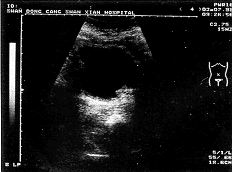

中国超声医学杂志990233 患者男,70岁。尿频、尿急并有血尿10天。超声检查:双肾大小、形态正常,实质回声可,肾窦无分离,内无异常回声,膀胱三角区探及1.6cm×0.8cm中等回声团块,形态不规则,后方无声影。变化体位时不移动(附图)。肝脏、胆囊、脾脏正常。超声诊断:膀胱占位。手术所见:膀胱三角区有一大小约1.6cm×0.8cm的肿块,向膀胱内突起,形态不规则,其他部位膀胱壁上有许多小结节状隆起。病理诊断:膀胱淀粉样变性。

附图 下腹部横切,显示膀胱肿块。